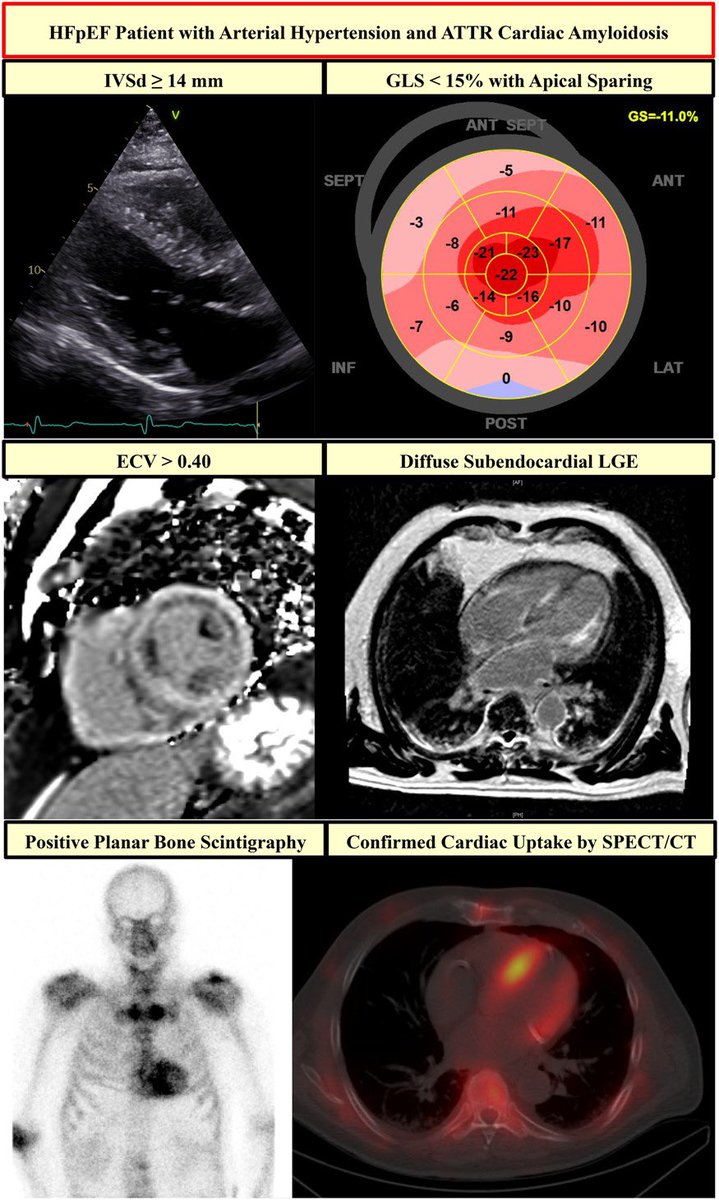

📌#whyCMR is the gold standard for imaging of cardiac structure and provides unique information about myocardial tissue characterization, such as the presence of scarring and fibrosis in the LV wall.

📌Nuclear imaging is gold standard for diagnosing #ATTR cardiac amyloidosis